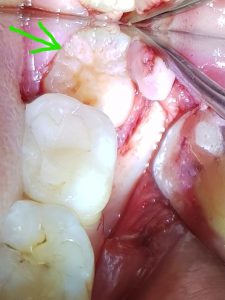

Deze jonge patiënt kwam bij mij met kiespijn in zijn linker onderkaak. Ook deed het tandvlees achter de laatste zichtbare kies pijn bij aanraken en poetsen. Bij controle van het tandvlees achter de laatste grote kies, kon ik met mijn instrument een hard voorwerp voelen onder het tandvlees:…..een verstandskies (groene pijl). We hebben meteen een Röntgenfoto gemaakt van deze regio en inderdaad zat er nog een verstandskies verscholen onder het tandvlees en in het bot (groene pijl). In de mond kon men, met het blote oog, de verstandskies niet zien. Door een toegang naar de verstandskies, langs de achterkant van de laatste kies tot onder het tandvlees, zijn bacteriën onder het tandvlees gekropen. Ze hebben het tandvlees rondom laten ontsteken en ze hebben een gaatje gemaakt in het voorste gedeelte van de verstandskies, bovenop het kauwvlak. Dit gaatje zat al tot in de zenuw, wat de kiespijn verklaarde.

Nadat we de kamer en onszelf gereed hadden gemaakt voor de operatie, ging ik en assistente Lucy aan het werk. Ik maakte een snede net links van het midden van het tandvlees dat over de verstandskies lag. Ik trok deze snede door langs de laatst zichtbare grote kies in de mond aan de wangkant en liet de snede vervolgens schuin naar voren in de omslagplooi eindigen. Zo klapte er een driehoekig stuk tandvlees opzij (triangular flap), waardoor de verscholen verstandskies en het bot waarin het zat, zichtbaar werden (groene pijl).